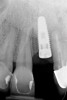

Clinical examination showed 2 mm of buccal recession with a shallow vestibule and absence of keratinized attached gingiva against the crown with 8 mm of circumferential pocketing accompanied by bleeding upon probing (Figure 15 and Figure 16). A periapical radiograph showed a symmetrical vertical osseous defect causing the loss of 50% of the bone around the implant (Figure 17). Because the patient had made a significant investment of time and finances to replace her lost tooth with the implant, she desired that the implant and restoration be retained, if feasible.

Fig 17. Radiograph showed symmetrical infrabony defect affecting 50% of the implant surface.